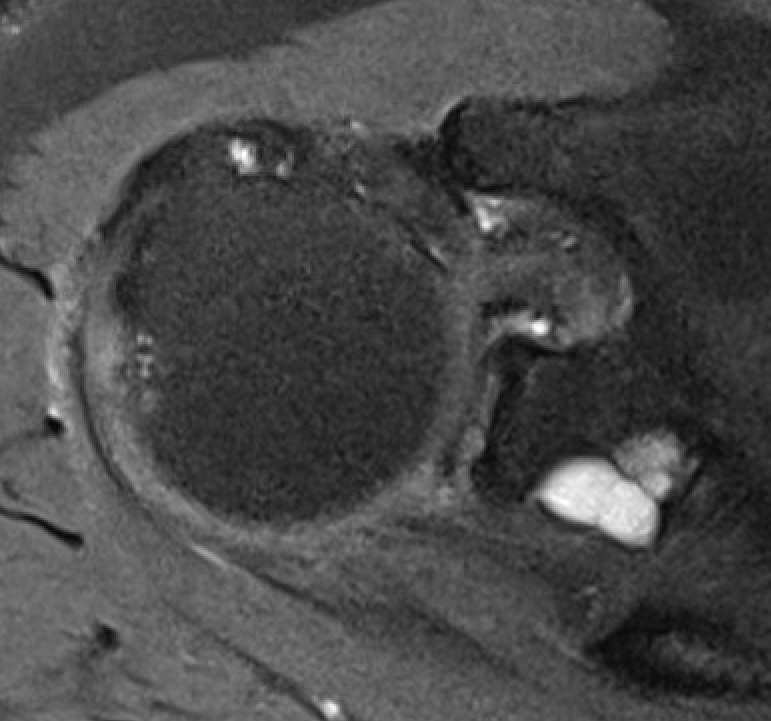

Spinoglenoid Cyst

MRI

Spinoglenoid cyst with SLAP tear and posterosuperior labral tear

Differential diagnosis

Posterior labral cysts secondary to glenohumeral OA